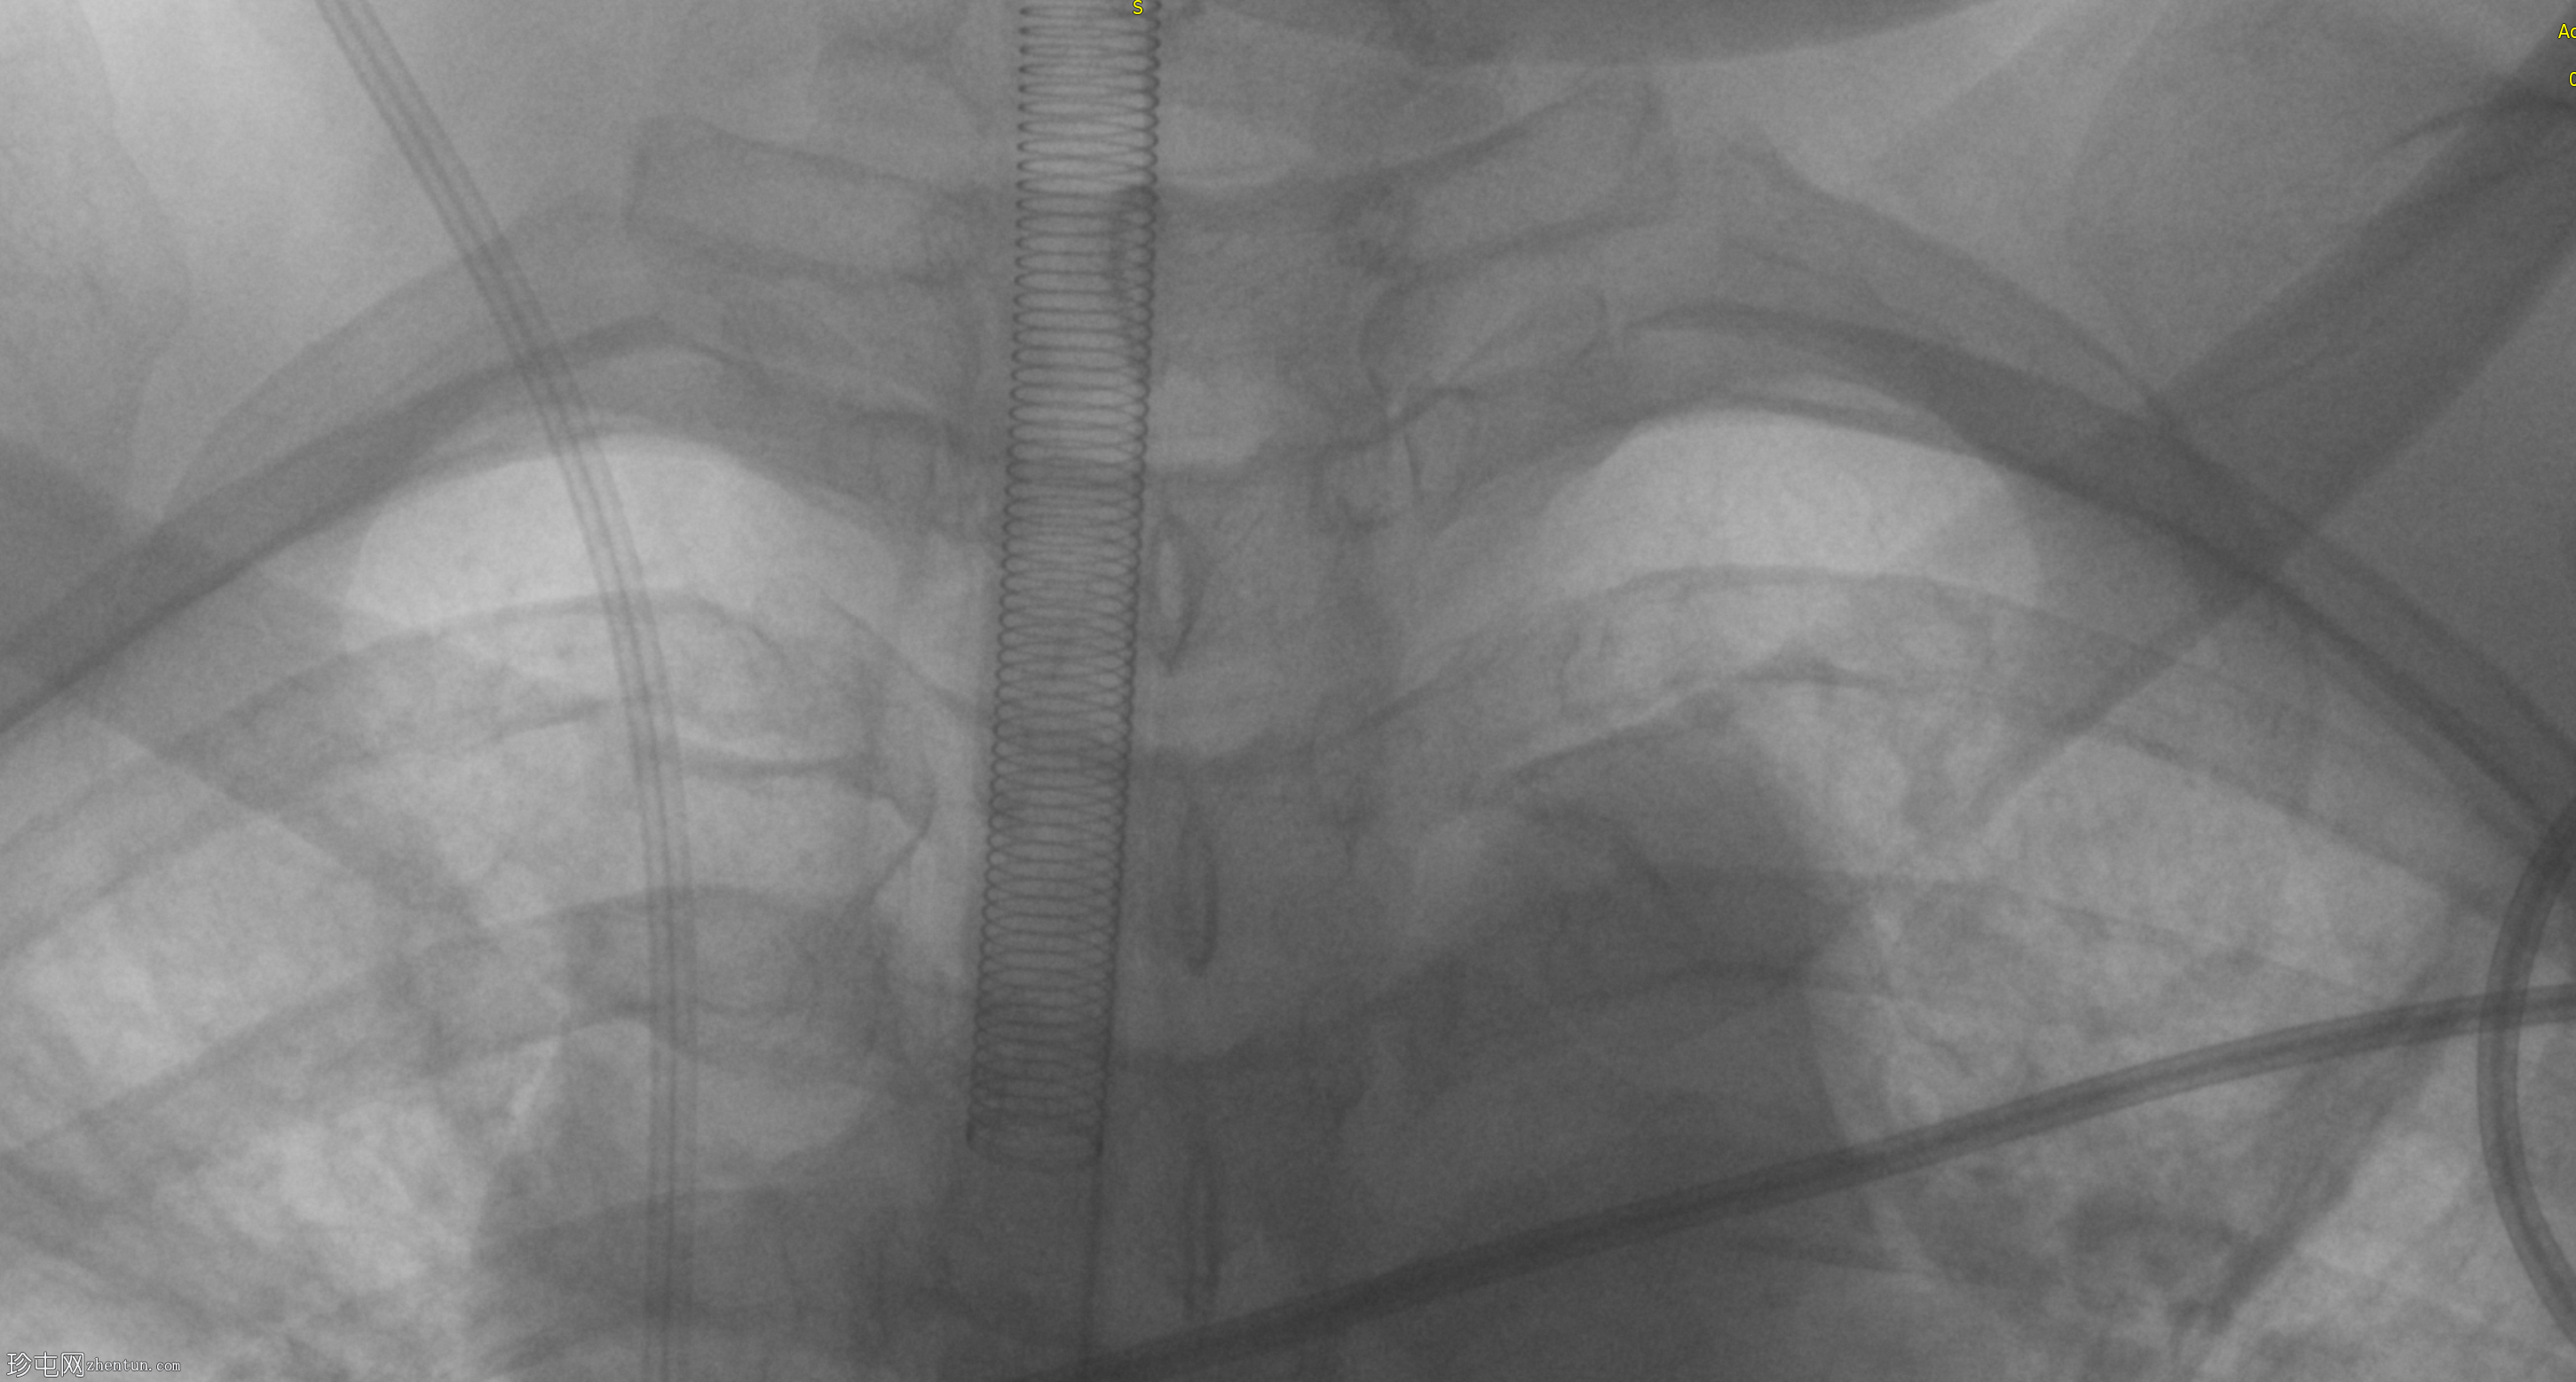

装甲气管插管 (ETT) 位置过深,需要回缩。

注意:加强型金属导丝末端靠近气管插管尖端。

铠装或加强型气管导管插入较深,建议回缩。

铠装或加强型气管导管因其柔韧性和强度,常用于颈部和胸部手术,例如本例。

关于加强型或铠装气管导管,重要的教学要点是,导线通常在导管尖端前1-2厘米处结束,例如本例,应仔细检查该处,以评估气管导管尖端的适用性。